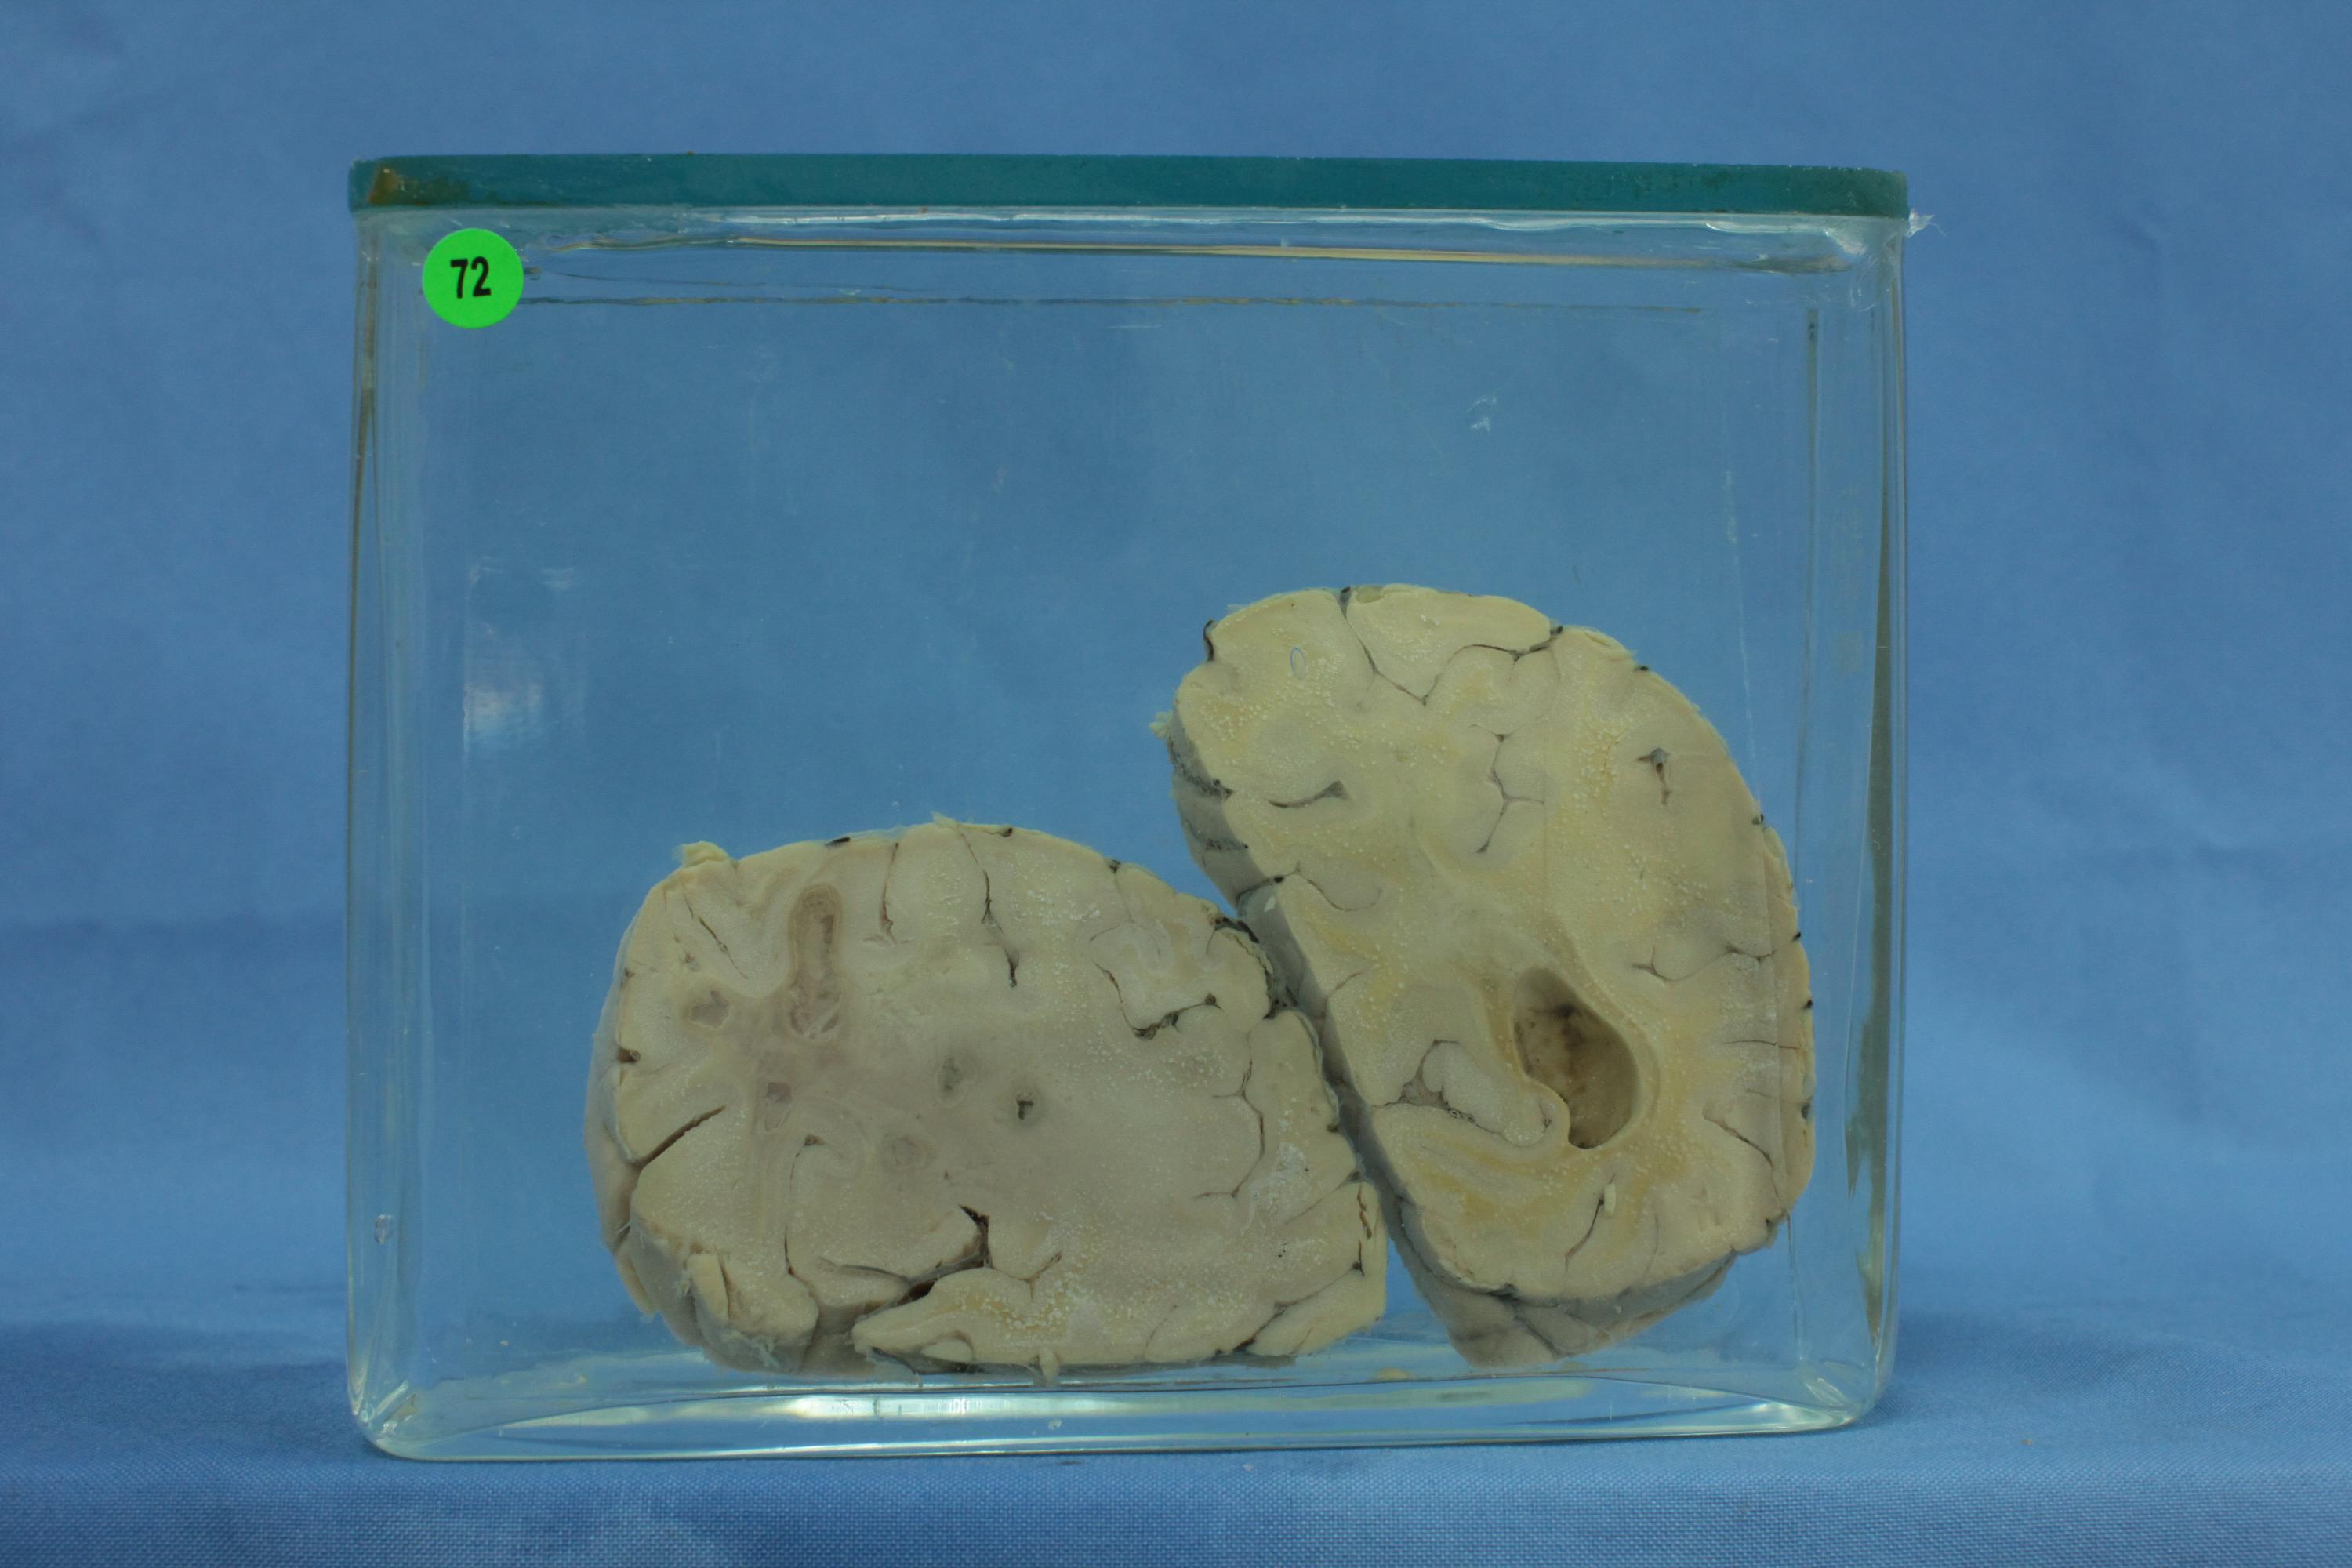

寄生虫病111-72. 脑肺吸虫病

患者男性,23岁,肺吸虫病。大脑冠状切面,脑实质内留有虫体穿行及暂时居留而形成互相沟通新旧不一的隧道及脓肿。